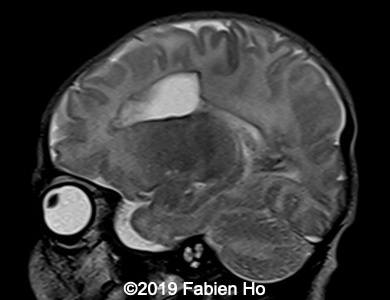

Images 1-3: in the left frontal lobe, hyperechoic with hypoechoic center lesion within the deep and periventricular white matter. Interestingly, this lesion has no mass effect on the lateral ventricle, and it has smooth margins.

Images 4-11, fetal brain MRI at 28 weeks: the left frontal lesion hence shows DWI hyperintensity, with T2* and T1 peripheral hyperintensity: ischemia with peripheral subacute hemorrhage. Note also that there is an associated blood clot in the left lateral ventricle. There is no obvious mass effect, nor peripheral edema. All these findin>gs are very suggestive of a clastic lesion.

Axial T2*w: T2* sequence is used in this case for its susceptibility to magnetic field inhomogeneity, i.e. to iron deposits for example. It is used to depict hemosiderin, which is roughly oxidized blood, i.e. “aged” blood. Blood MRI signal evolves as time passes.